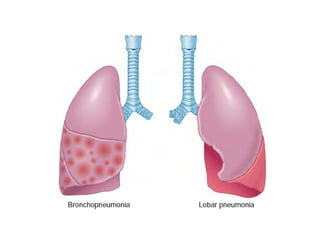

MORPHOLOGY

• LOBAR vs. BRONCHO

• “HEPATIZATION”, RED vs. GREY

• CONSOLIDATION

• “INFILTRATE”, XRAY vs. HISTOPATH

• Loss of “CREPITANCE”

MORPHOLOGY • LOBAR vs.BRONCHO • “HEPATIZATION”, RED vs. GREY • CONSOLIDATION • “INFILTRATE”, XRAY vs. HISTOPATH • Loss of “CREPITANCE”

• #13 Do the upper two images demonstrate the “lobar-ness” of the pneumonia? Ans: Yes; GRAM POSITIVE DIPLOCOCCI